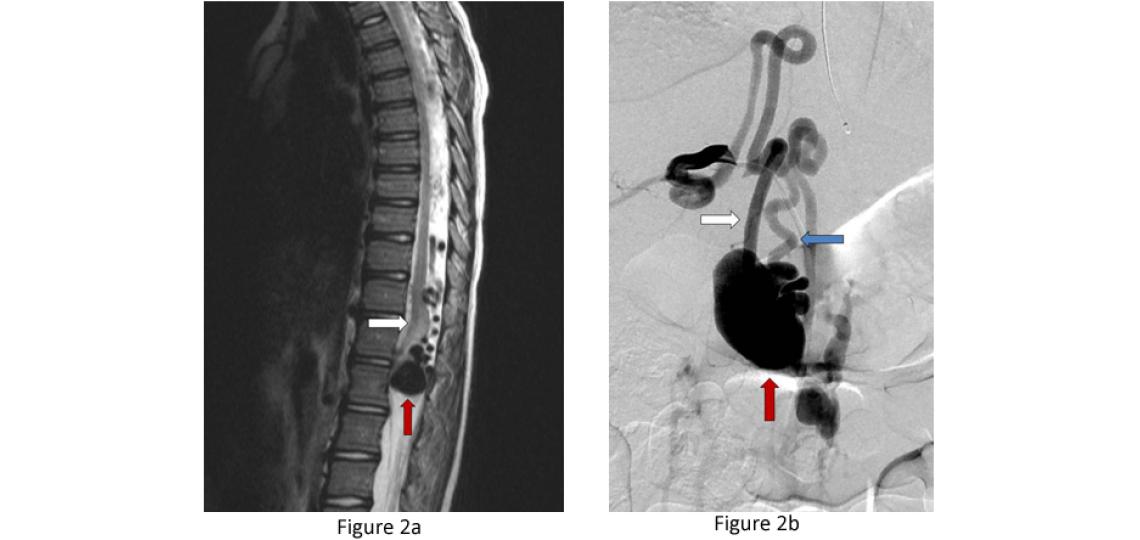

Spinal Dural Arteriovenous Fistulas (Type I) - These malformations represent 70 percent of spinal vascular malformations and are the result of an abnormal connection forming between an artery and a vein in the spinal canal dural covering (Figure 1). This connection allows high pressure arterial blood to escape into the low pressure network of veins draining the spinal cord. Over time, the spinal cord is damaged by the elevated pressure. Spinal dural fistulas form spontaneously during adulthood and are not congenital or hereditary. These lesions do not rupture or bleed. They are good candidates for surgical treatment.

Figure 1a: Type I dural AV fistula - spinal angiogram of a left sided spinal artery (white arrow) showing an abnormal connection (red arrow) with a spinal vein that has become abnormally enlarged (blue arrow). Figure 1b: Similar view of the same fistula using a 3D flat panel CTA reconstruction showing greater detail of the abnormal artery-venous connection within in the nerve root dural sleeve (red arrow) and enlarged vein within the spinal canal (blue arrow). Figure 1c: Side or sagittal view of the same fistula showing the enlarged vein (blue arrow) along the back wall of the spinal canal behind the spinal cord.